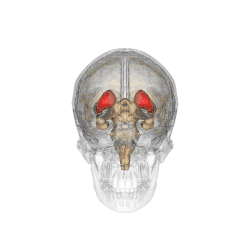

Caudate nucleus

Caudate nucleus (in red) shown within the brain

Caudate nucleus within the skull